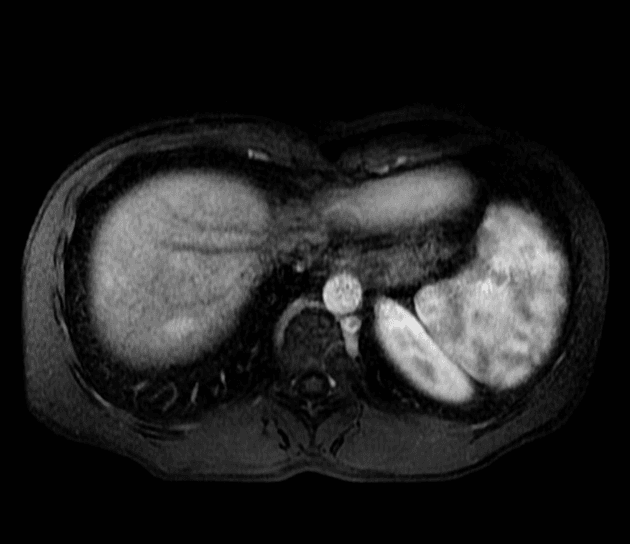

Chụp cộng hưởng từ theo dõi

Không có bằng chứng của bệnh lý nhu mô gan.

Hai tổn thương khu trú ở gan được xác định:

Một tổn thương rất nhỏ thấy ở vùng dưới màng gan của phân đoạn IVa phía trước, chỉ quan sát thấy rõ ở thì động mạch, nguyên nhân và ý nghĩa chưa rõ.

Đường mật không giãn. Tụy, thận, tuyến thượng thận, lách có hình dạng bình thường. Không có dịch tự do hoặc bệnh lý hạch.

Kết luận: Hai tổn thương khu trú ở gan, hình ảnh cộng hưởng từ phù hợp với tăng sản khu trú dạng nốt (focal nodular hyperplasia).

Hai tổn thương bắt thuốc ở phân đoạn 6 và 3, vùng trung tâm giảm tỷ trọng (không bắt thuốc) và không có hiện tượng thải thuốc (washout).

Hình ảnh điển hình của tăng sản khu trú dạng nốt (focal nodular hyperplasia), là một trong số ít các tổn thương có khả năng tích tụ mạnh thuốc cản quang đặc hiệu tế bào gan.